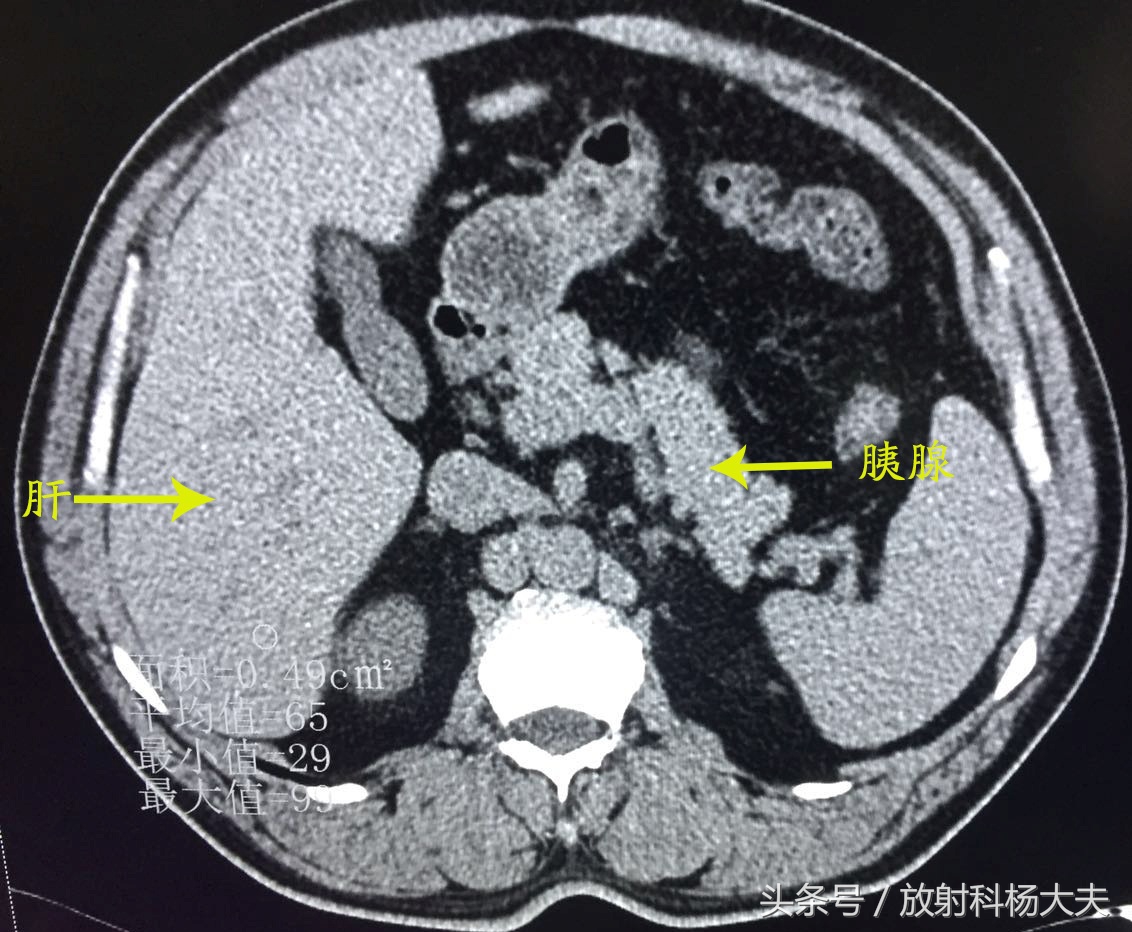

我即刻查阅了他既往的片子,果然,一年前因为腹痛就诊过,CT检查如下:

CT图像可见肝脏密度弥漫性减低,明显低于同层面脾脏密度,胰腺饱满,周围可见渗出样改变---急性胰腺炎伴重度脂肪肝。

当时治疗后复查:

胰周渗出基本吸收了,脂肪肝较前也有所好转了。